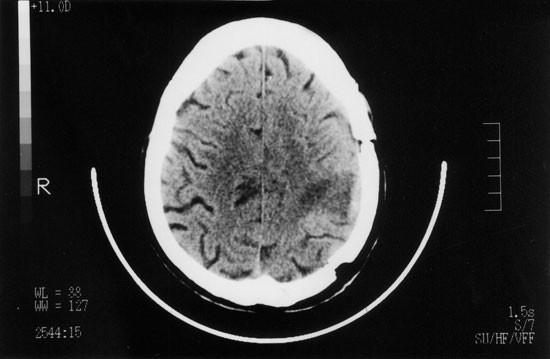

In February 1997, after two severe infectious episodes (Figure 1), he was readmitted with a 2-week history of fever, non-productive cough, exertional dyspnea and weight loss. White blood count was 3.3 × 109/l, the absolute lymphocyte count was 472/mm3 and absolute neutrophil count was above 1.0 × 109/l. A chest X-ray and a CT scan revealed bilateral alveolar infiltrates. Broncho-alveolar lavage (BAL) disclosed Mycobacterium tuberculosis. Drug-sensivity testing did not show criteria of a multidrug-resistant strain. Treatment with isoniazide, rifampin and pyrazinamide was begun. Fever disappeared in a few days and his general condition improved. In May 1997, he presented with headache, dysarthria, papilledema, and signs of a third cranial nerve palsy. CT scan of the brain revealed a large lesion, involving the right temporal lobe (Figure 2). Cultures (blood, sputum, CSF) were negative. Serology tests for toxoplasmosis were negative. Biopsy of the brain lesion disclosed an extensive infiltrate by acid-fast bacilli, later identified by PCR as Mycobacterium tuberculosis. Drug-sensivity testing was not feasible because cultures were inadvertently contaminated. The mass was excised, antituberculous treatment was maintained and immune suppression was continued. Despite neurosurgical sequelae seen on a CT scan of the brain performed 1 month later (Figure 3), neurological recovery was complete. In November 1997 the patient died of septic shock caused by E. coli infection. All throughout the post-transplant period he remained in molecular remission with full donor chimera.